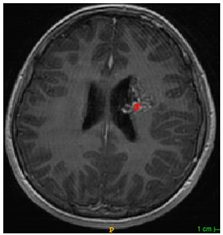

Three cases from the NTUH dataset showing representative results of different models were shown in Table 2, Table 3 and Table 4. The overall dice scores of these networks on the NTUH dataset ranged from 0.33 (DeepMedic) to 0.51 (V-Net). Table 5 shows the detailed performance of each network tested with the NTUH dataset.

Table 2.

Predictions with low dice scores.

Table 3.

Predictions with average dice scores.

Table 4.

Predictions with high dice scores.